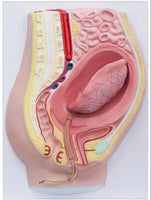

Modelo de desprendimiento separacion de placenta

Este modelo es una sección sagital del abdomen y la cavidad pélvica femenina con volumen uterino y superficie de inserción pélvica reducidos después del parto, que muestra la estructura morfológica del útero, la vagina, la placenta y el cordón umbilical.

Las superficies fetal y materna de la placenta tienen una forma realista, la parte inferior del útero está ligeramente hacia arriba y continúa contrayéndose, cerca del bulto abdominal inferior de la sínfisis del pubis y el cordón umbilical que cuelga en los genitales (signos de desprendimiento de placenta). ).

se desprende la parte central de la placenta y se baja al segmento inferior de la cavidad uterina.